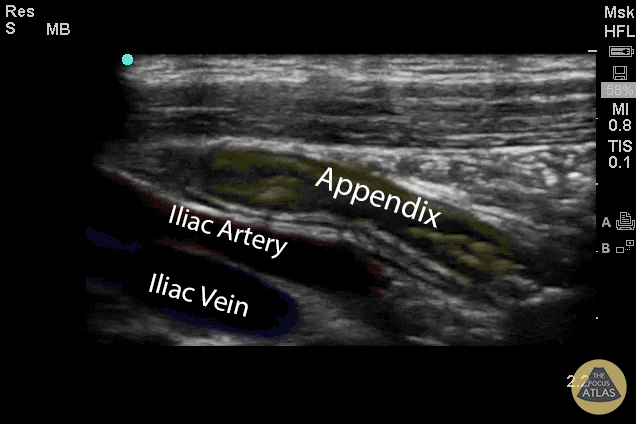

Colorized Appendicitis Images - Labeled and Colorized Appendix and Landmarks (Longitudinal)

Images provided by Sathya Subramaniam - Children’s Hospital of Philadelphia, edited by Matthew Riscinti - Kings County Emergency Medicine